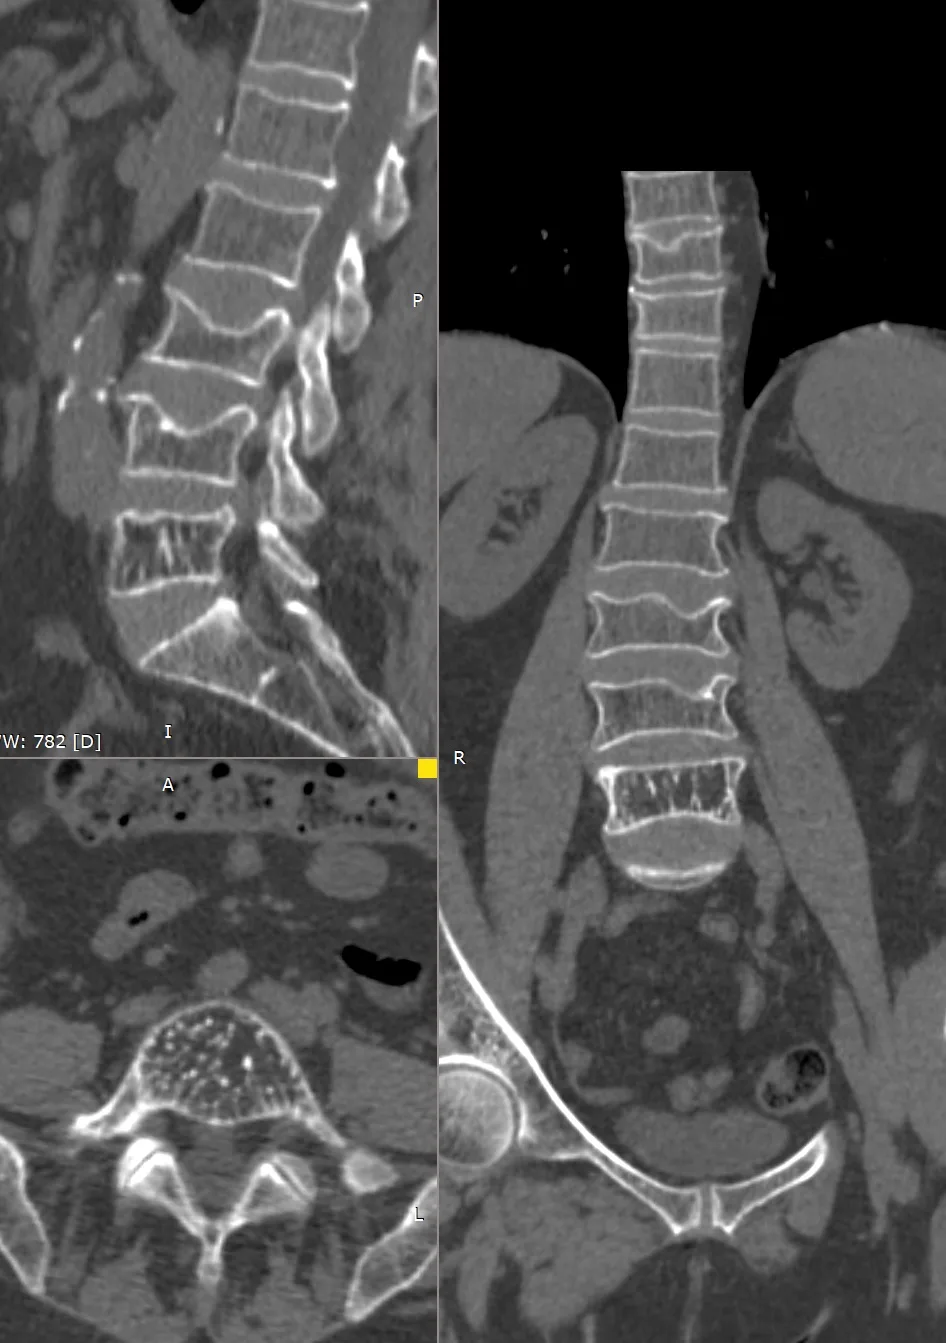

Ещё один прекрасный пример стойкости позвонков, в которых имеется гемангиома, у которой, в свою очередь, имеются очень крупные и плотные трабекулы, по всей видимости, они и не дают позвонку сломаться даже при развитии остеопороза. Пациенту 65 лет, множественные патологические переломы позвонков на фоне остеопороза, а позвонок с гемангиомой практически не изменён. К вопросу о профилактическом цементировании…